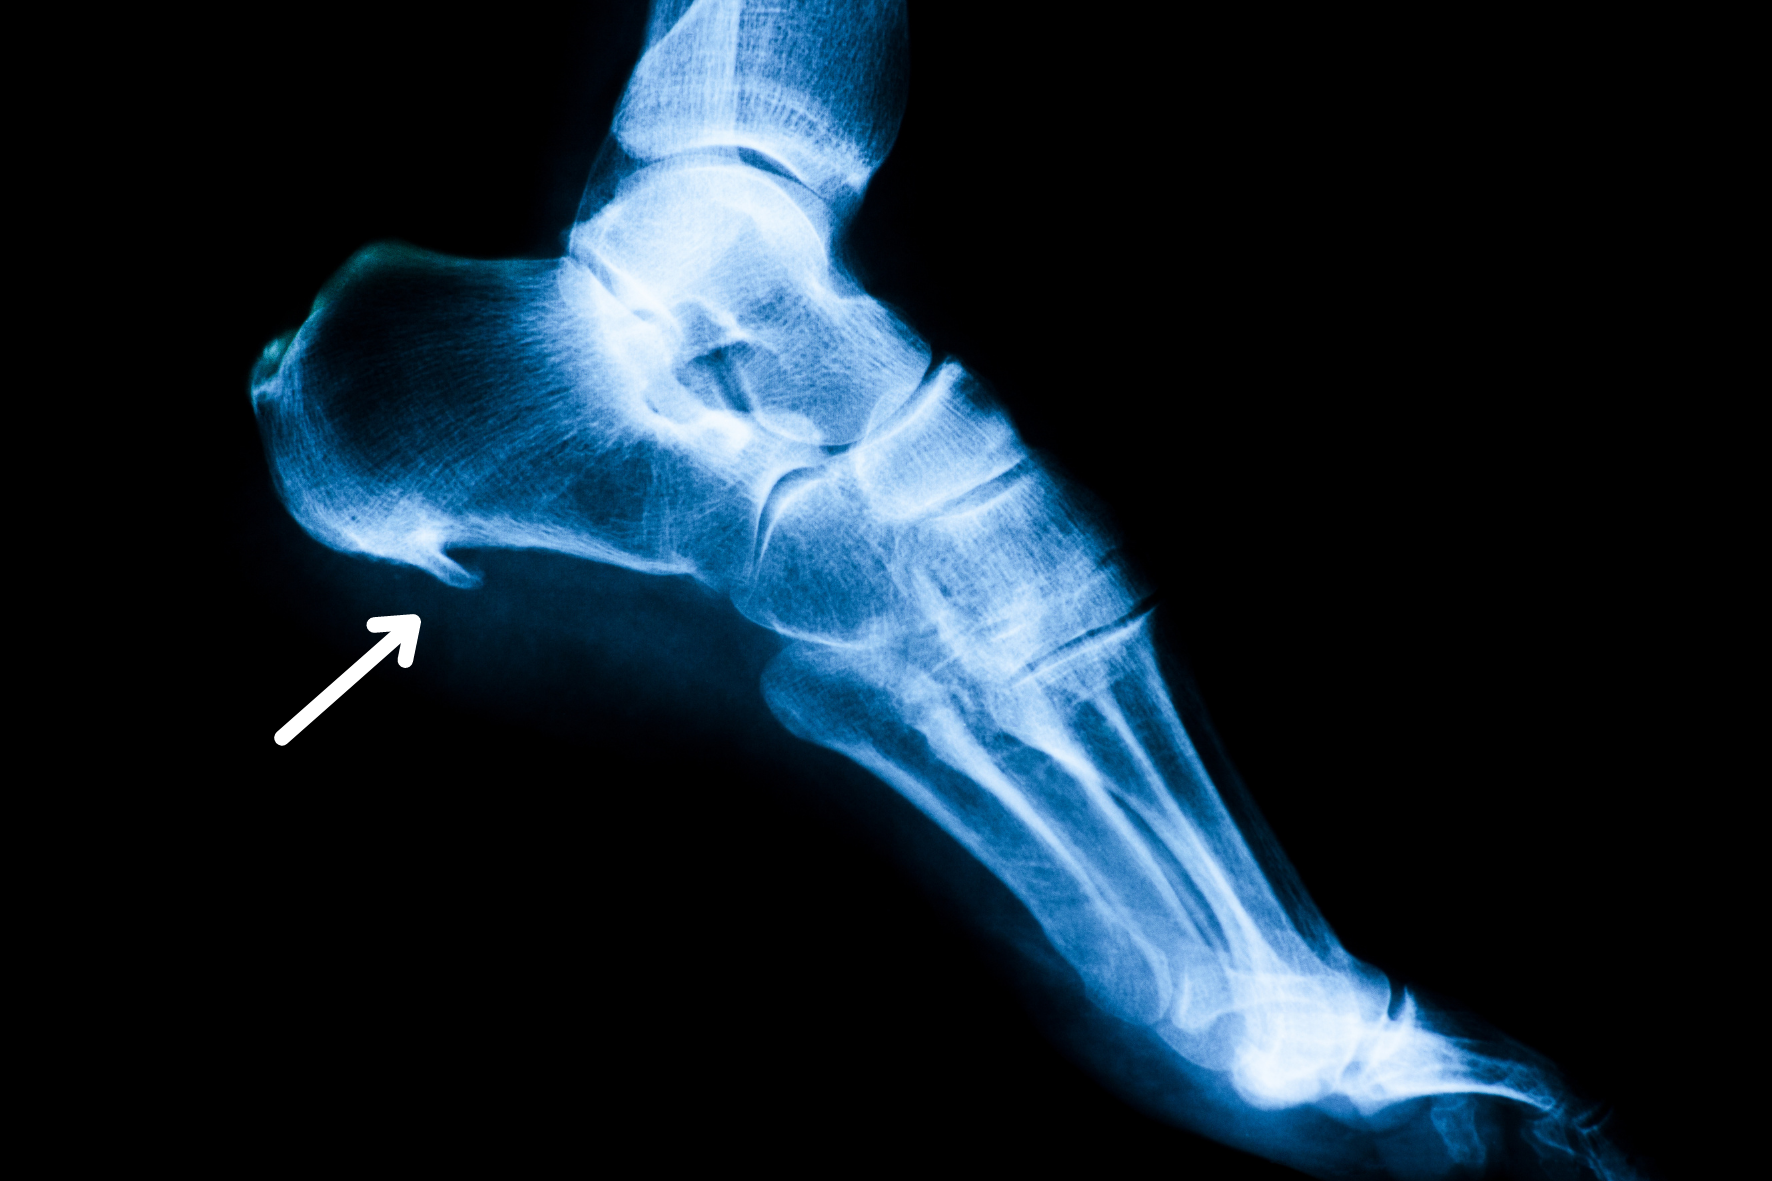

Hælspore røntgen

Hvis svangsenen, der løber under foden fra hælens forreste del til bag på tæerne, over længere tid er for spændt, kan det indledningsvis skabe en inflammation med tilhørende smerte. Kroppen vil, hvis ikke problemet forsvinder, prøve at forstærke hæftepunktet på hælen ved at danne en lille knogleudvækst – en spore. Den er som sagt egentlig ment fra kroppens side til at forstærke området, men samtidig skaber den problemer. En knogleudvækst er i sagens natur stiv, og er der noget, man ikke har brug for i det område, så er det stivhed. Der er brug for fleksibilitet, for at vi kan gå og løbe. Som følge af denne mismatch kommer der en inflammation, og det er den, der skaber smerten.